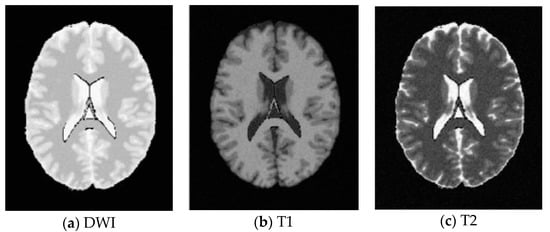

SBD: The database has DWI, T1 and T2 images of size 181 × 217 pixels. In our experiments, the classification results were quantified based on the ground truth of SBD. We added Rician noise to the analog image. In our experiments, the SNR (signal to noise ratio) values were set to 10 dB, 5 dB, 15 dB, and 20 dB, respectively. Shown in Figure 7, Figure 8, Figure 9 and Figure 10 are SBD images.

Figure 10. SBD Images with SNR = 20 dB.

Entropy 20 00964 g010